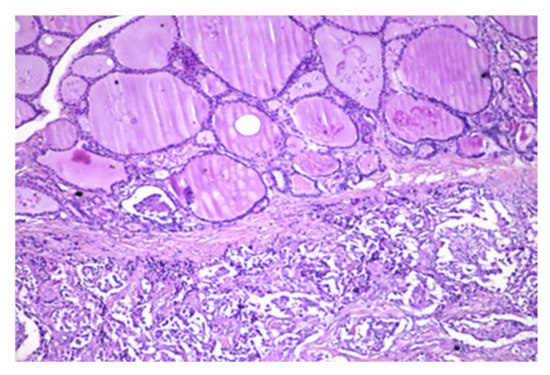

4.2. Histopathology Features